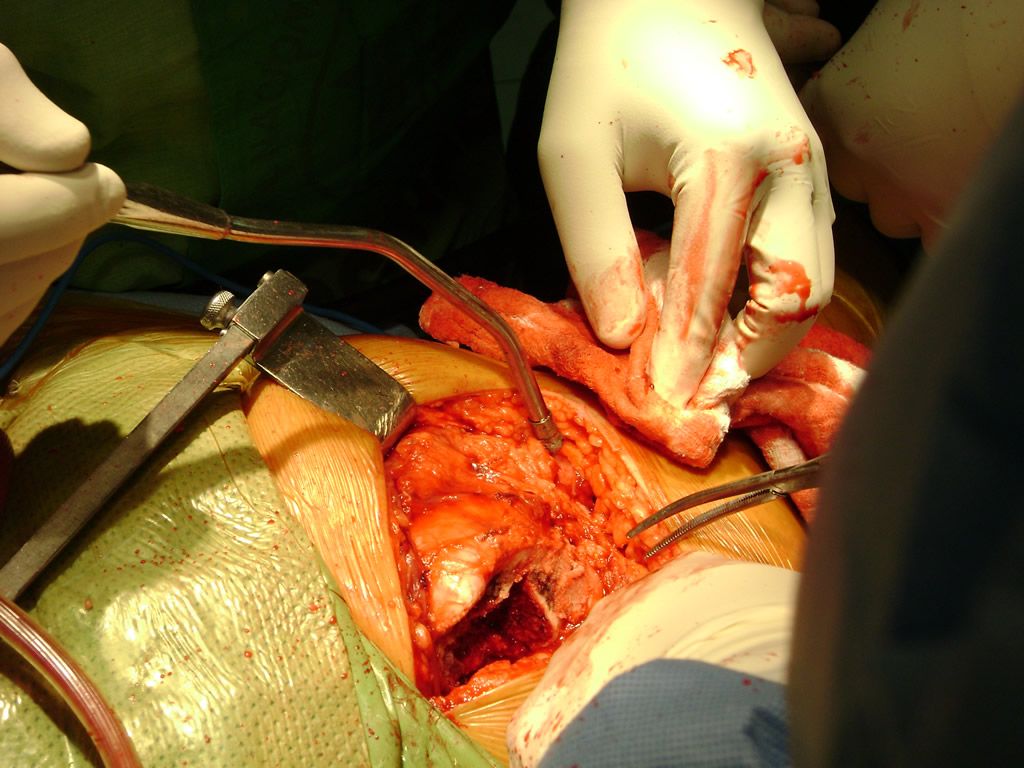

Debido a la fina cobertura de piel que recubre la tibia y el peroné, las fracturas generalmente son abiertas, es decir, el hueso roto rasga la piel, atravesándola. Las fracturas de tibia y peroné generalmente se producen por un fuerte impacto o torsión.